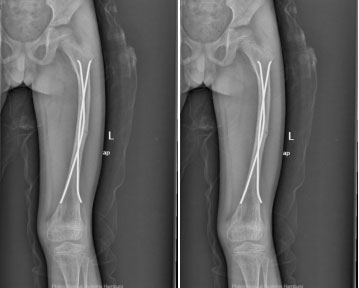

上圖為患者9歲時(shí)第2次股骨干骨折術(shù)后影像學(xué)資料